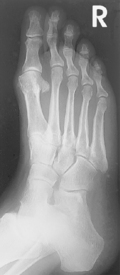

• Supine or seated with foot centered lengthwise to portion of IR being exposed

• Oblique foot 30°–40° medially, support with 45° radiolucent angle block and sandbags to prevent slippage

• Note 1: A higher arch requires nearer 45° oblique and a low arch “flat foot” nearer 30°.

• Note 2: A 30° lateral oblique projection will demonstrate the space between 1st and 2nd metatarsals and between 1st and 2nd cuneiforms.